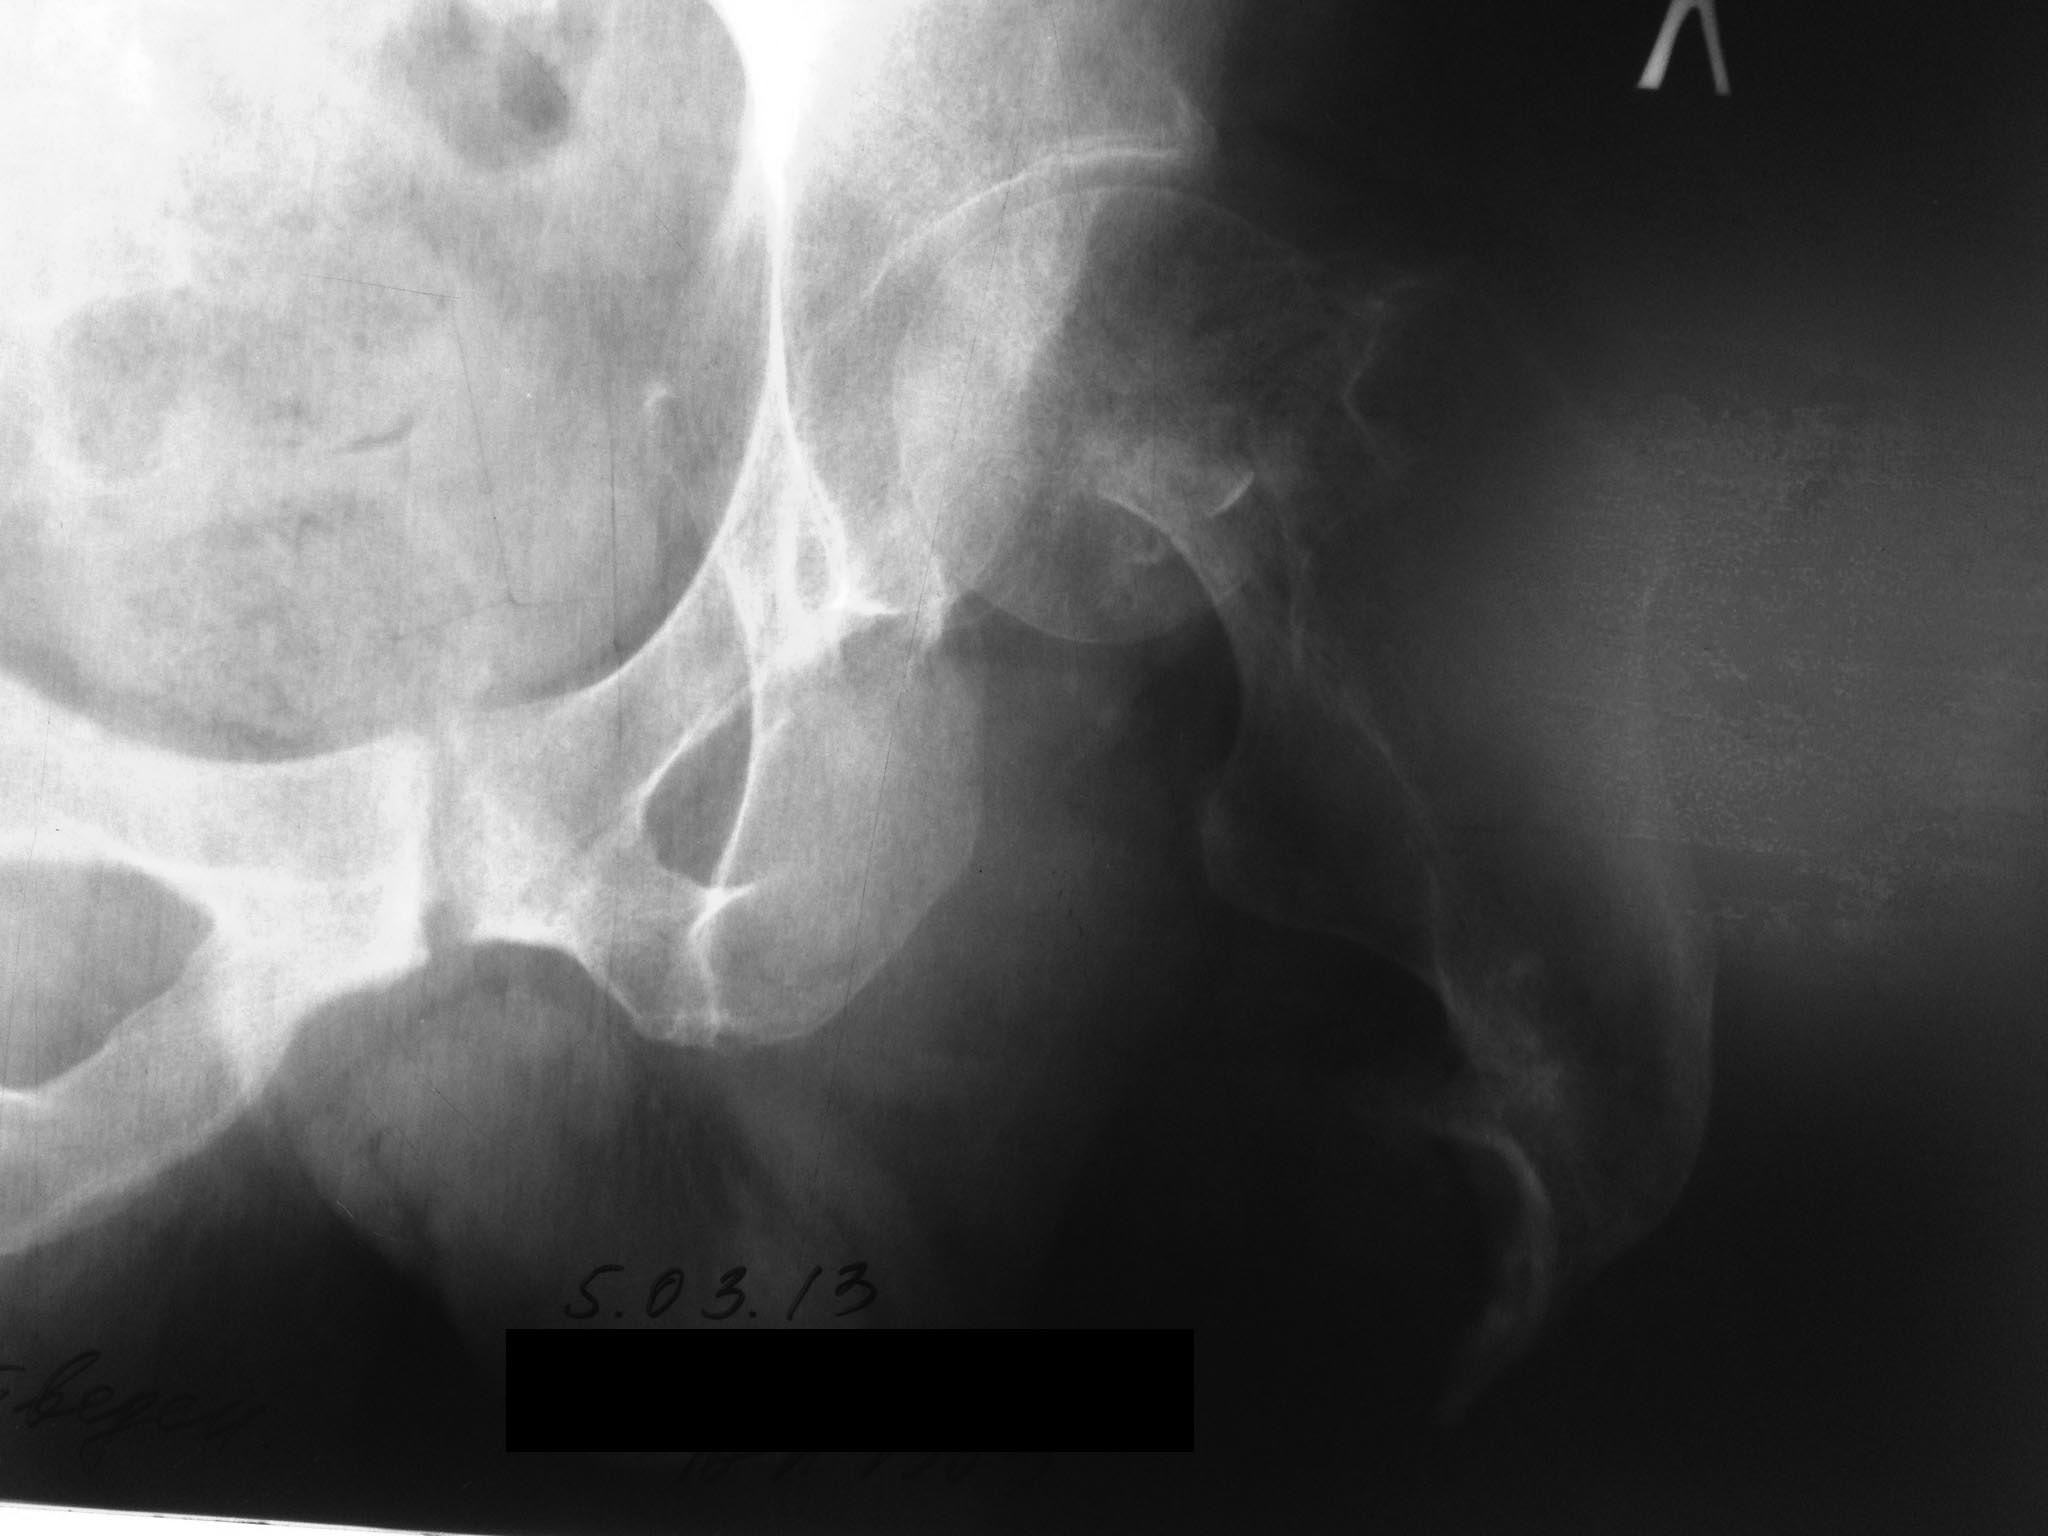

Здравствуйте, коллеги! Пациент 54 лет в середине 80х ампутация бедра во

время боевых действий. В течении 30 лет использование экзопротеза,

работал водителем. Три месяца назад перелом шейки бедра.

В настоящее время внешний протез не опорен из за боли. Возможно ли

поставить эндопротез?

Какую лучше ножку? Стандартные короткие ножки ( Nanos) отпадают из- за

пороза и короткой культи шейки. Может укоротить во время операции по

длине культи ножку типа Corail? Насколько выше риск вывиха из- за

непредсказуемого мышечного баланса?